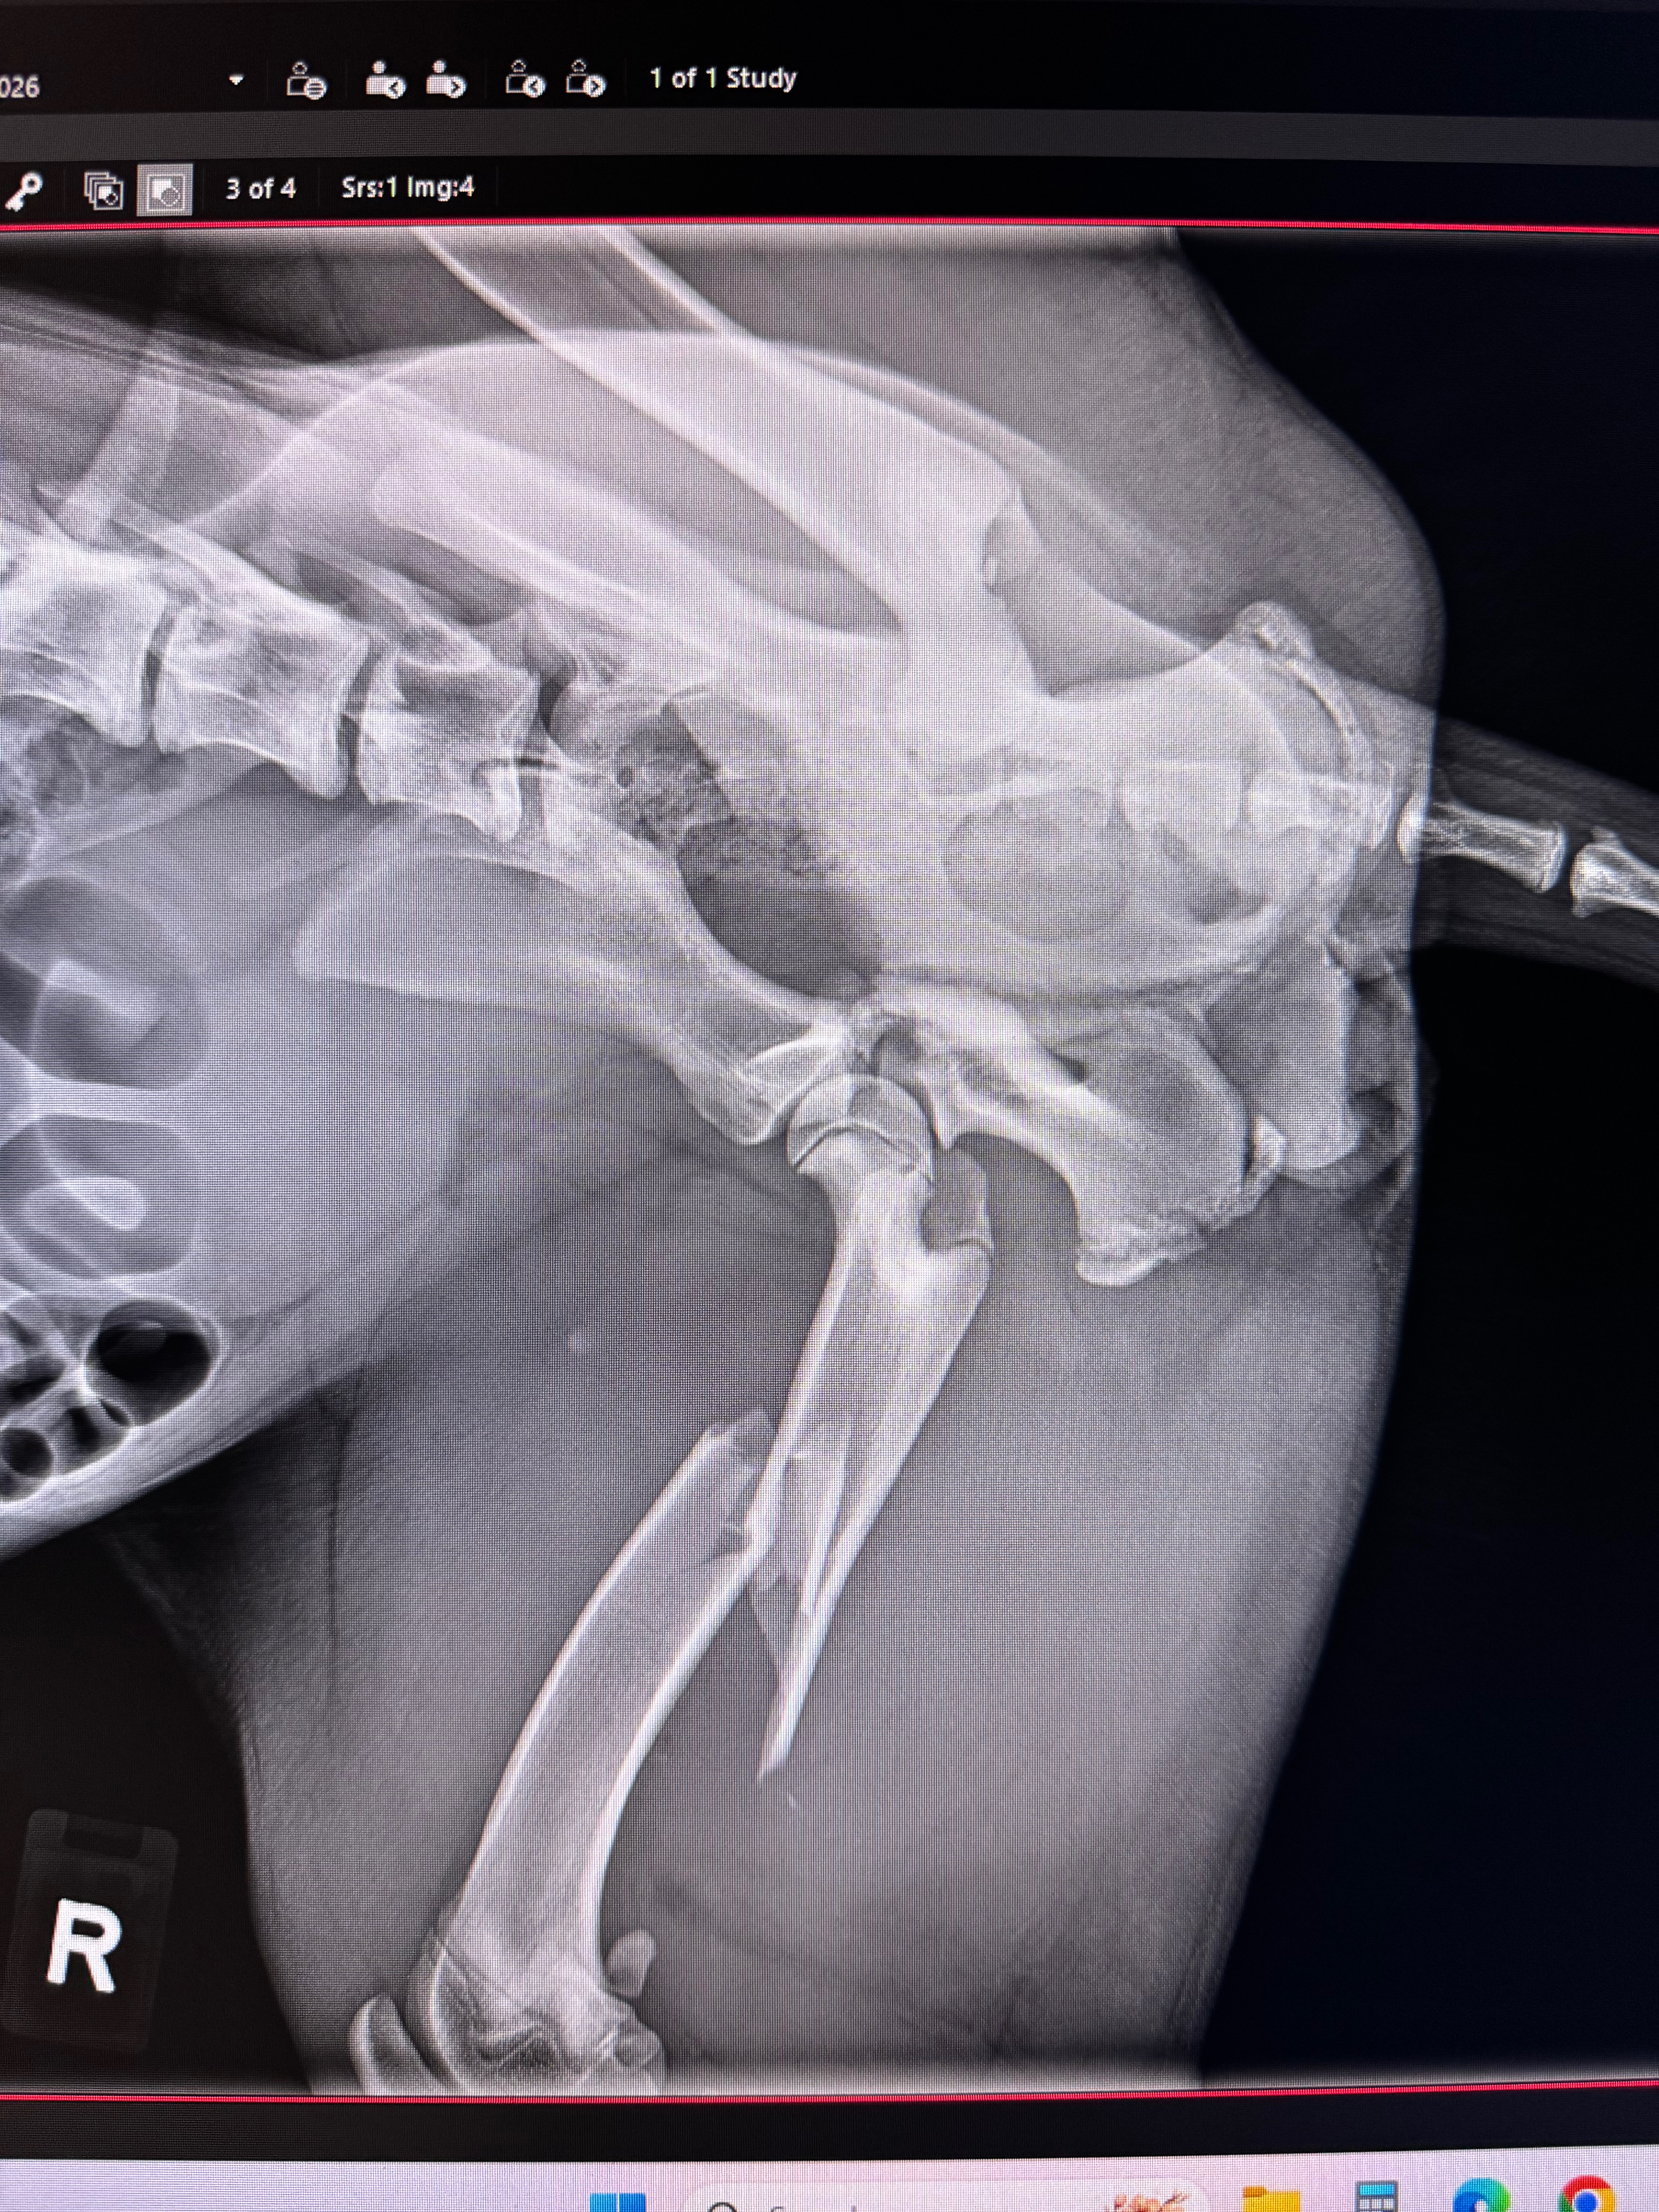

My pet is facing a heartbreaking decision between having her leg amputated or being put down. She has broke 3 different parts of her leg and would need extensive surgery to even be able to think about walking. She's only 6 months old, has already survived parvovirus and this situation has just come on so suddenly. She has brought so much joy and love into our lives in such a short time, and it’s heartbreaking to think of losing her so soon. We never expected to be in this position, but we are determined to do everything we can to give her a fighting chance.

The funds raised will go directly toward her surgery, aftercare, and physical therapy. We want to make sure she has the opportunity to recover and thrive, despite the challenges she’s facing. We do feel since she's young she can make the adjustment to live as a 3 legged baby. Your support will help cover the medical costs, provide her with the care she needs to heal, and give her the best possible quality of life moving forward. Every little bit helps, and your kindness can truly make a difference for her.